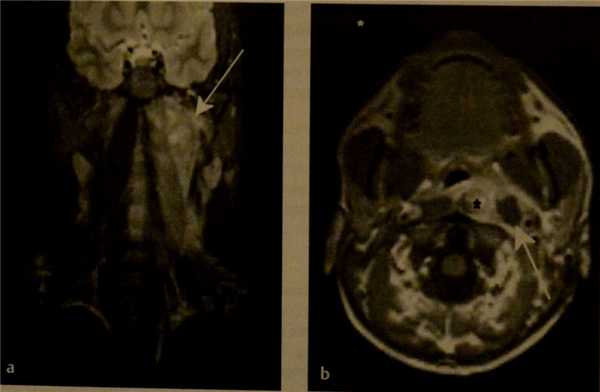

3. МРТ при нагноении заглоточных лимфоузлов:

• Т2ВИ:

о Заглоточный лимфоузел с диффузным или локальным участком высокой интенсивности

о Повышение интенсивности сигнала окружающих тканей

• ДВИ:

о Ограничение диффузии в нагноившемся лимфоузле

• Т1ВИ с КУ:

о Накопление контраста в лимфоузле и окружающих тканях

(Слева) КТ с КУ, аксиальная проекция. Ребенок пяти месяцев жизни. В заглоточном пространстве имеется скопление жидкости неправильной формы, распространяющееся в левую половину пространства. Вероятнее всего, гной прорвался из лимфоузла. Обратите внимание на наличие двусторонней шейной лимфаденопатии без признаков нагноения.

(Справа) МРТ Т1ВИ FS с КУ, аксиальная проекция. У ребенка имеется аллергия на йодсодержащий контраст. В правой половине заглоточного пространства четко визуализируется абсцесс. Окружающие ткани интенсивно накапливают контрастное вещество.